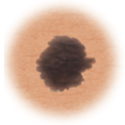

Melanoma

Sign

Characteristic